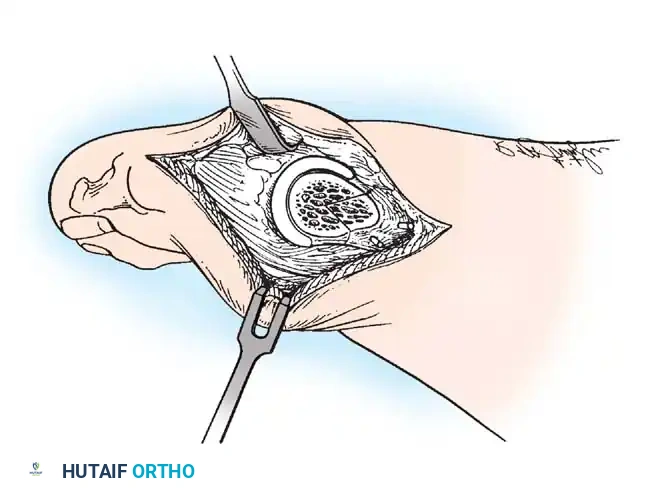

Modifi ed McBride Bunionectomy TECHNIQUE 78-1

SKIN AND CAPSULAR INCISION

• With the patient supine and a tourniquet on the limb, extend a midline, straight, medial incision from the middle of the proximal phalanx to 2 cm proximal to the junction of the medial eminence with the metatarsal shaft (Fig. 78-13). This incision usually is in an internervous plane between the most medial branches of the superfi cial peroneal nerve dorsally and the medial proper digital branch of the medial plantar nerve plantarward. (McBride recommended a single incision beginning at the fi rst web space and extending proximally and medially across the metatarsal, ending on the medial side of the fi rst metatarsal proximal to the exostosis.)

• Mobilize the skin 2 to 3 mm dorsally and plantarward to ensure that no sensory nerve would be injured by the capsular incision.

• Coagulate the superfi cial veins as encountered to minimize postoperative bleeding.

• Use delicate, two-tooth retractors and 1.5-mm forceps in this initial dissection to avoid unnecessary skin trauma.

• Make a longitudinal capsular incision (the original McBride capsular incision was transverse) 3 to 4 mm plantar to the line of the skin incision (Fig. 78-14).

Fig. 78-14 Modifi ed McBride procedure. Longitudinal capsular incision is 3 to 4 mm plantar to skin incision.

• By sharp dissection, raise the periosteum and the capsule dorsally and plantarward from the base of the proximal phalanx to the proximal edge of the medial eminence (Fig. 78-15). At the proximal end of the medial eminence, avoid releasing the proximal bony attachments of the medial capsule on the metatarsal neck (especially in the dorsal direction) in an attempt to expose the medial eminence. To ensure adequate exposure without disruption of this proximal attachment, a longitudinal capsular incision is suggested.

• Elevate the capsule by sharp dissection dorsalward and plantarward to expose the dorsal aspect of the metatarsal head, the entire medial eminence, and the plantar plate. A periosteal elevator is not recommended because of the possibility that the proximal attachments of the capsule may be released.

L-SHAPED CAPSULAR INCISION

• Alternatively, make the capsular incision in an inverted L shape (Fig. 78-16A).

• Raise the dorsal fl ap deep to the nerve and veins until the accessory slip of the extensor hallucis longus tendon is seen in the proximal portion of the incision where it is easier to identify. The tendon almost always can be located with careful searching. If it is not seen at the dorsomedial aspect of the fi rst metatarsal, however, begin the longitudinal limb of the incision at this slope of the metatarsal from dorsal to medial.

• Begin the incision proximally on the dorsomedial side of the fi rst metatarsal shaft and 2 to 3 mm medial to the accessory slip of the extensor hallucis longus tendon. Carry the incision to the bone at the level of the fi rst metatarsal joint, extending proximally 4 to 6 cm.

• Make the transverse limb of the capsular incision at the level of the joint, stopping 2 to 3 mm from the tibial sesamoid bone; this limb transects the capsular insertion of the abductor hallucis muscle (Fig. 78-16B and C).

Fig. 78-15 Modifi ed McBride procedure. Capsule is opened, and attachment of capsule on metatarsal neck (arrow) is carefully preserved.

• Beginning on the plantar aspect of the incision, remove the capsule from the medial eminence from the inside out. Avoid buttonholing the capsule at the junction of the medial eminence and the metatarsal by directing the small-bladed knife down the slope of the eminence.

• Free the capsule subperiosteally on its dorsomedial surface, and retract it proximally and plantarward (Fig. 78-16D).

• Insert one small Hohmann retractor over the dorsolateral surface of the metatarsal head and another beneath the head at the head and neck junction, while distracting and plantar fl exing the hallux to expose the articular surface of the metatarsal head for evaluation of its condition and orientation. Reduce the hallux congruently on the metatarsal head.

• If the hallux is in more than 15 degrees of valgus after reduction, a distal metatarsal osteotomy is needed.

MEDIAL EMINENCE REMOVAL

• After inspecting the metatarsophalangeal joint for degenerative changes, loose bodies, or synovial abnormalities, remove the medial eminence by fi rst scoring with an osteotome its proximal edge where the eminence meets the shaft. Always consult the preoperative radiographs to determine how much of the medial eminence should be removed.

• Using the same osteotome or a power saw, begin the exostectomy distally at the parasagittal groove, and direct it medially toward the scored area on the metatarsal shaft (Fig. 7817). If a power saw is used, a 9-mm blade, rather than a 4to 5mm blade, is preferred. The medial direction of the osteotomy prevents splitting of the metatarsal shaft, especially if the proximal edge of the osteotomy has been scored as recommended.

• After the medial eminence has been removed, use a small rongeur to round off the dorsal and plantar edges of the medial aspect of the metatarsal head. Rasping the raw bone concludes the initial stage of the procedure. Use bone wax on the raw surfaces of bone of the metatarsal head.

ADDUCTOR TENDON AND LATERAL CAPSULAR RELEASE

• Begin the second stage with a dorsal longitudinal incision beginning 2 to 3 mm proximal to the dorsal aspect of the fi rst web space to avoid web contracture postoperatively; extend it proximally between the fi rst and second metatarsal heads for 3 to 4 cm (Fig. 78-18). This allows adequate exposure of the adductor insertion into the base of the proximal phalanx, the lateral head of the fl exor hallucis brevis muscle converging on the fi bular sesamoid, and the entire lateral capsule from the extensor hallucis longus muscle to the plantar plate.